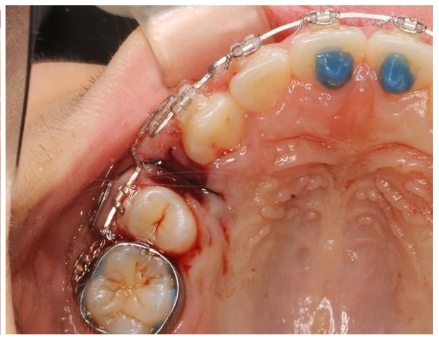

X-ray of the post-extraction site.

This image has an empty alt attribute; its file name is image-12.png X-ray of the post-extraction site.

Once the Interproximal Reduction spaces were closed, it was time to extract the bicuspids, and the bracket was removed to facilitate the extraction. The first bicuspids were extracted, and the new MEAW closing wire was applied to close the extraction space. Activation was performed immediately after extraction. Figure 12 shows the current situation immediately after the extraction was completed. Between the canine and the second bicuspids, after the first bicuspids have been removed, the rapid acceleration phenomenon (RAP) and the low density of the remaining alveolar bone facilitate tooth movement. The retention that affects this movement is primarily located in the alveolar bone near the apex of the canine. The rate of tooth movement depends on the roots and their morphology; the periodontal membrane and alveolar bone structure may vary at each tooth’s center of resistance.